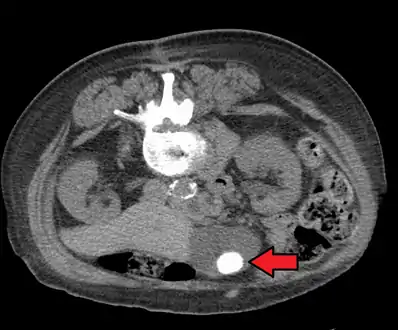

A 1.9 cm gallstone impacted in the neck of the gallbladder and leading to cholecystitis as seen on ultrasound. There is 4 mm gall bladder wall thickening.

Large gallstone as seen on CT- A normal gallbladder on ultrasound with bowel peristalsis creating the false appearance of stones